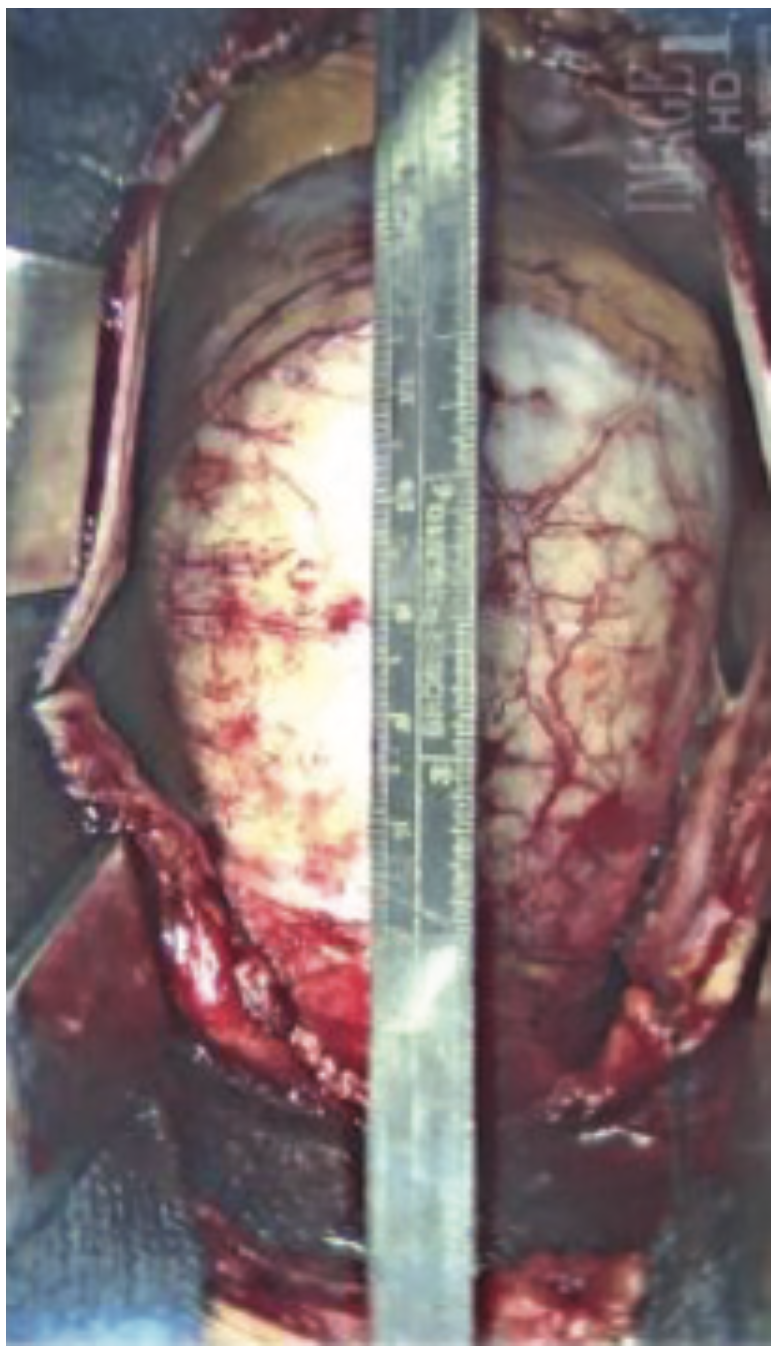

She was widowed, lived alone, and quit smoking 4 years ago, with a 40 pack-year smoking history. Her family history was non-contributory. She had noticed some dyspnea on exertion during routine chores such as mowing the lawn and carrying laundry upstairs, which she attributed to deconditioning. She was otherwise asymptomatic, even during her episode of supraventricular tachycardia (SVT) during her recent colonoscopy. During her TTE, the technologist notified the cardiologist of a 9-centimeter ascending aortic aneurysm, effacing the sinotubular junction with dilated sinuses of Valsalva. The TTE also demonstrated moderate aortic regurgitation. There was no evidence of vegetation or aortic dissection, or pericardial effusion. The patient was admitted to the University Hospital from the office for further management. A computed tomography scan of the chest with contrast was done in the emergency department to further define the aneurysm. Cardiac catheterization was performed the following day, revealing normal coronaries, normal left ventricular systolic function, and a 9-centimeter ascending aortic aneurysm. She underwent urgent cardiothoracic surgery. The surgeon repaired her aortic root with a Dacron patch and replaced her aortic valve with a bioprosthetic pericardial aortic valve. The patient had an otherwise unremarkable post-operative course, primarily consisting of blood pressure control. She was discharged with surgical follow-up within 1 week and cardiology follow-up in 2 weeks.

Thoracic aortic aneurysms are usually approached with surgical repair using a cardiopulmonary bypass and an aortic root replacement.4 Basic principles of a TAA repair are to sew to healthy tissue, replacing the aortic arch if there is no pathology, extending the hemi-arch replacement of the proximal arch if it is involved, and total arch replacement if the entire arch is aneurysmal.7 Aortic grafts made of Dacron are used due to their tensile strength and rate of tissue ingrowth.7 The post-operative course and follow-up are dependent upon any surgical complications and patient comorbidities. Hospitalization for TAA repair is between 7 to 10 days, although this is dependent on post-surgical complications.7 Follow-up imaging is performed at 1, 3, 6, and 12-month intervals.7 Afterwards, if the aorta is stable, only yearly imaging is needed.